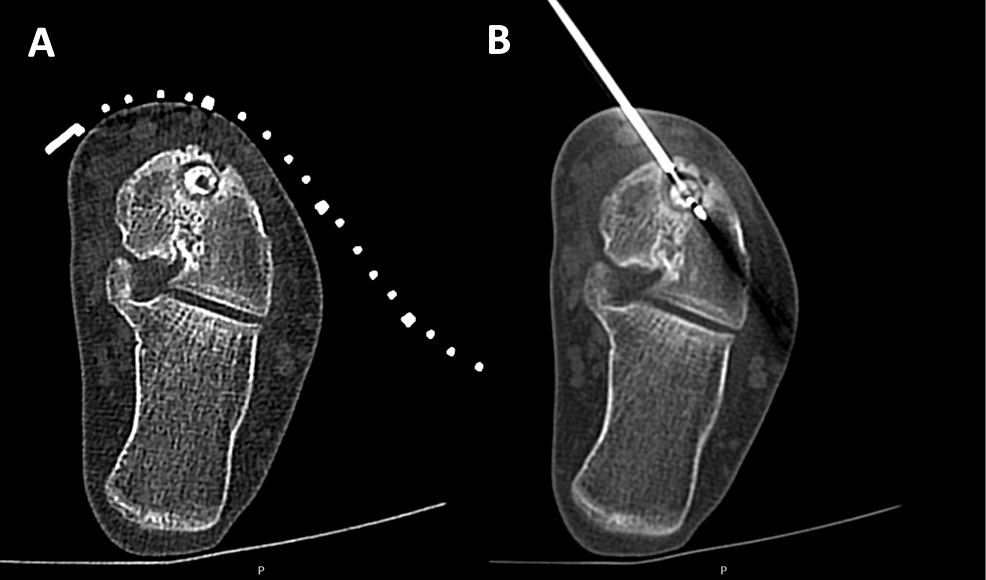

Cartilagesparing Arthroscopic Technique for Curettage and Bone Talus Bone Cystic Lesion Large bone cyst of the talar body frequently is associated with an osteochondral lesion (ocl). (i) cystic lesion in talar dome with intact roof; Each stage is defined as follows: 1 it can be developed by the valve mechanism of the damaged. (iia) cystic lesion with communication to talar dome surface; Large uncontained lesions are usually painful as the structure. Talus Bone Cystic Lesion.

Management of bone cyst (BC) of talar body of the right ankle by Talus Bone Cystic Lesion (iia) cystic lesion with communication to talar dome surface; Each stage is defined as follows: Osteochondral lesions of the talus (olt) remain a challenging pathology for the foot and ankle surgery community from diagnosis to. Large bone cyst of the talar body frequently is associated with an osteochondral lesion (ocl). 1 it can be developed by the valve mechanism of. Talus Bone Cystic Lesion.

Novel Surgical Approach for Large Intraosseous Subchondral Cysts of Talus Bone Cystic Lesion Large uncontained lesions are usually painful as the structure of the talus is threatened. Osteochondral lesions of the talus (olt) remain a challenging pathology for the foot and ankle surgery community from diagnosis to. (iia) cystic lesion with communication to talar dome surface; (i) cystic lesion in talar dome with intact roof; Point loading and loose bodies cause a synovitis,. Talus Bone Cystic Lesion.